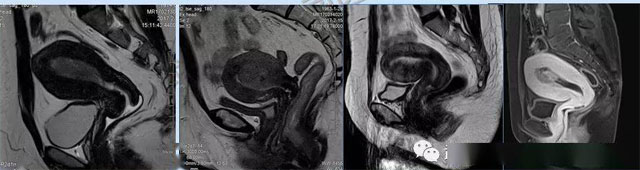

婦科疾病常常讓女性陷入了焦慮。主要是這類疾病婦女有難言之隱,癥狀隱匿,病情復雜。磁共振體檢車的金光火眼能力可以破解各種婦科難題。哪些情況需要使用磁共振檢查,檢查過程是否有不適。這些都是可以解決的。例如子宮常見疾病的磁共振診斷。

磁共振VS傳統(tǒng)檢查:有這些優(yōu)勢?無輻射安全系數(shù)高,磁共振沒有電離輻射,適合備孕跟孕婦檢查。它對軟組織有高清的成像效果,可以清晰的看到子宮各層的結(jié)構??梢宰R別細小的肌瘤,早期的癌癥腫瘤??梢园l(fā)現(xiàn)其他設備難以檢查到的深部子宮內(nèi)膜異位結(jié)節(jié)。多序列成像和增強掃描檢查,判斷腫瘤的良性準確率高達90%以上。

磁共振檢查可以對子宮內(nèi)膜癌,精準測量腫瘤侵犯子宮肌層的深度,發(fā)現(xiàn)微小轉(zhuǎn)移灶。復雜子宮肌瘤明確肌瘤位置、數(shù)量,區(qū)分良性肌瘤與惡性肉瘤,幫助制定微創(chuàng)手術方案。卵巢腫瘤鑒別數(shù)值分析、增強掃描,可識別畸胎瘤、巧克力囊腫、惡性腫瘤的特征。宮頸癌分期,判斷腫瘤大小、是否侵犯膀胱/直腸,指導選擇手術或放化療。生殖道畸形三維成像直觀顯示畸形類型,為矯正手術或輔助生殖提供依據(jù)。